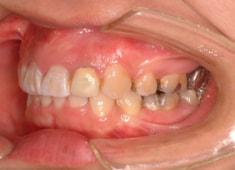

治療開始時